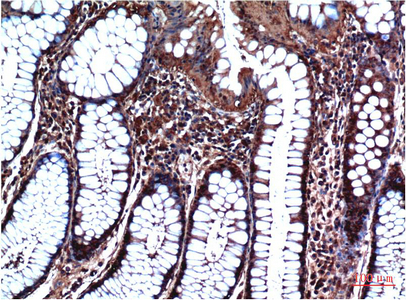

- Immunohistochemical analysis of paraffin-embedded Human tonsils using GSK3 beta antibody.High-pressure and temperature Sodium Citrate pH 6.0 was used for antigen retrieval.